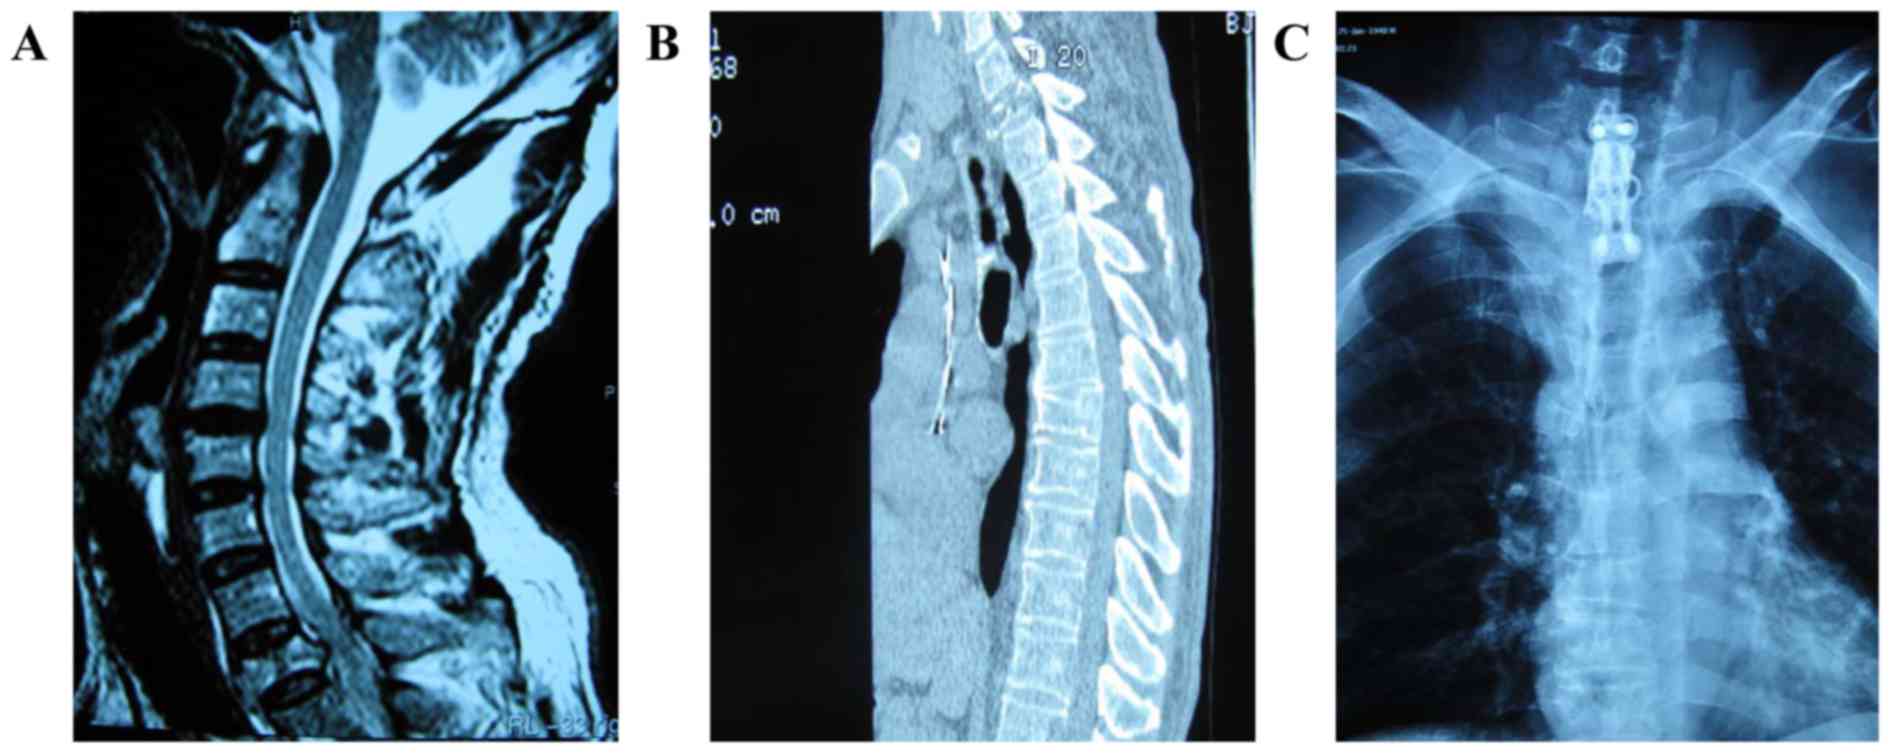

Figure 2.

Images from one patient from group A. (A) Magnetic resonance imaging examination demonstrated that the lesion was located in the ventral vertebral body of the first thoracic, and the destroyed part of the vertebral body bulged backward and compressed the dural sac. Image obtained prior to surgery. (B) Computed tomography scan revealed that the majority of the first thoracic vertebrae had been destroyed. Image obtained prior to surgery. (C) The lesion and the destroyed vertebral body were removed via an anterior approach, and were reconstructed with a titanium cage, bone cement and instrumentation with a vertebral body screw. Image obtained following surgery.